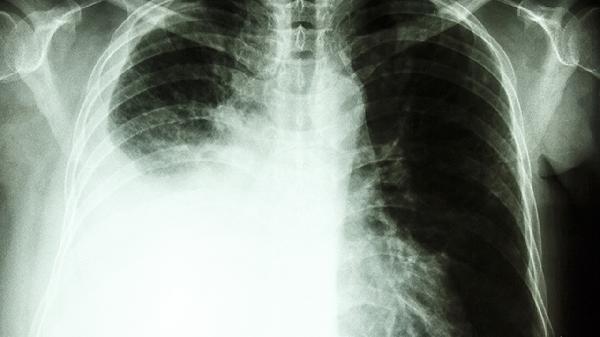

3、肺癌早期可能表现为肺部结节或气泡,需要进一步通过CT扫描、PET-CT或活检确诊。治疗方式包括手术切除、放疗和化疗,具体方案需根据肿瘤类型和分期制定。

肺上气泡是否癌变需通过专业医学检查明确,早期发现和干预是关键。无论是良性还是恶性病变,及时就医并遵循医生建议进行治疗和生活方式调整,都能有效改善预后。